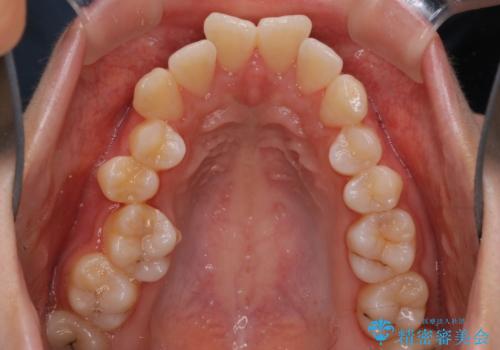

【抜歯インビザ】凸凹を綺麗になおしたい

- 前歯の凸凹を主訴に来院されました。

叢生量が多いため、抜歯が必要となるため、ワイヤー矯正をお勧めしましたが、患者さんの希望によりインビザラインで治療を開始しました。途中でワイヤーリカバリーを必要とせず終了でき患者さんには満足していただけました。